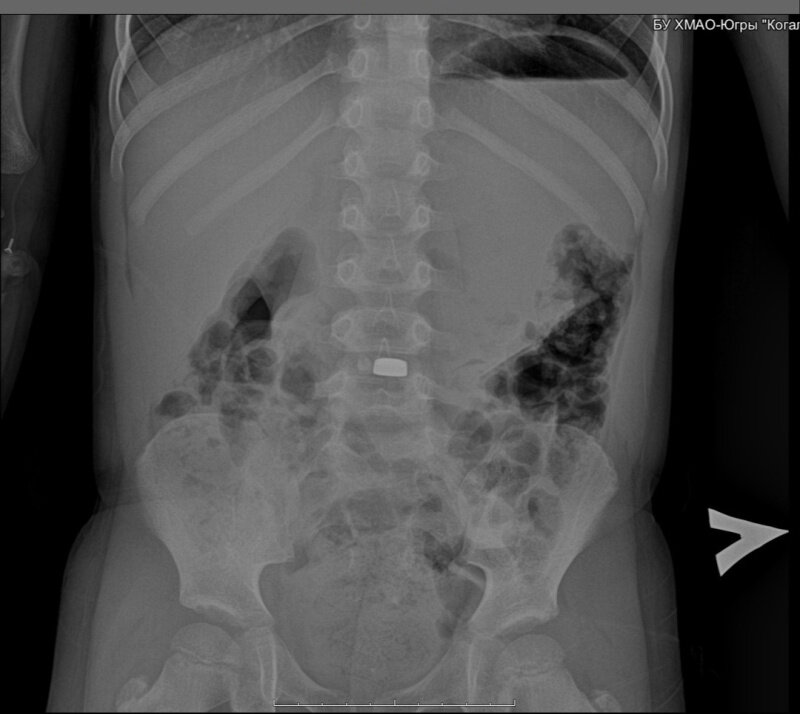

По информации окружного депздрава, для уточнения диагноза малыш был направлен на проведение рентгенологического исследования. На рентгенологическом снимке было диагностировано инородное тело округлой формы диаметром 22 мм.

«Учитывая малый возраст ребенка – 5 лет, возможность опасности действия электрического элемента на живые ткани желудка, было принято решение о незамедлительном удалении данного инородного тела. Последствия могут быть губительны для ребенка: из поврежденной батарейки вытекает электролит, и уже через несколько часов наступает ожог и некроз окружающих тканей», - разъяснил врач - хирург Гусейн Мусаев.